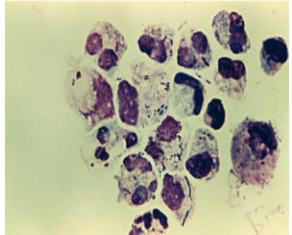

mestasis (blasts)

blasts